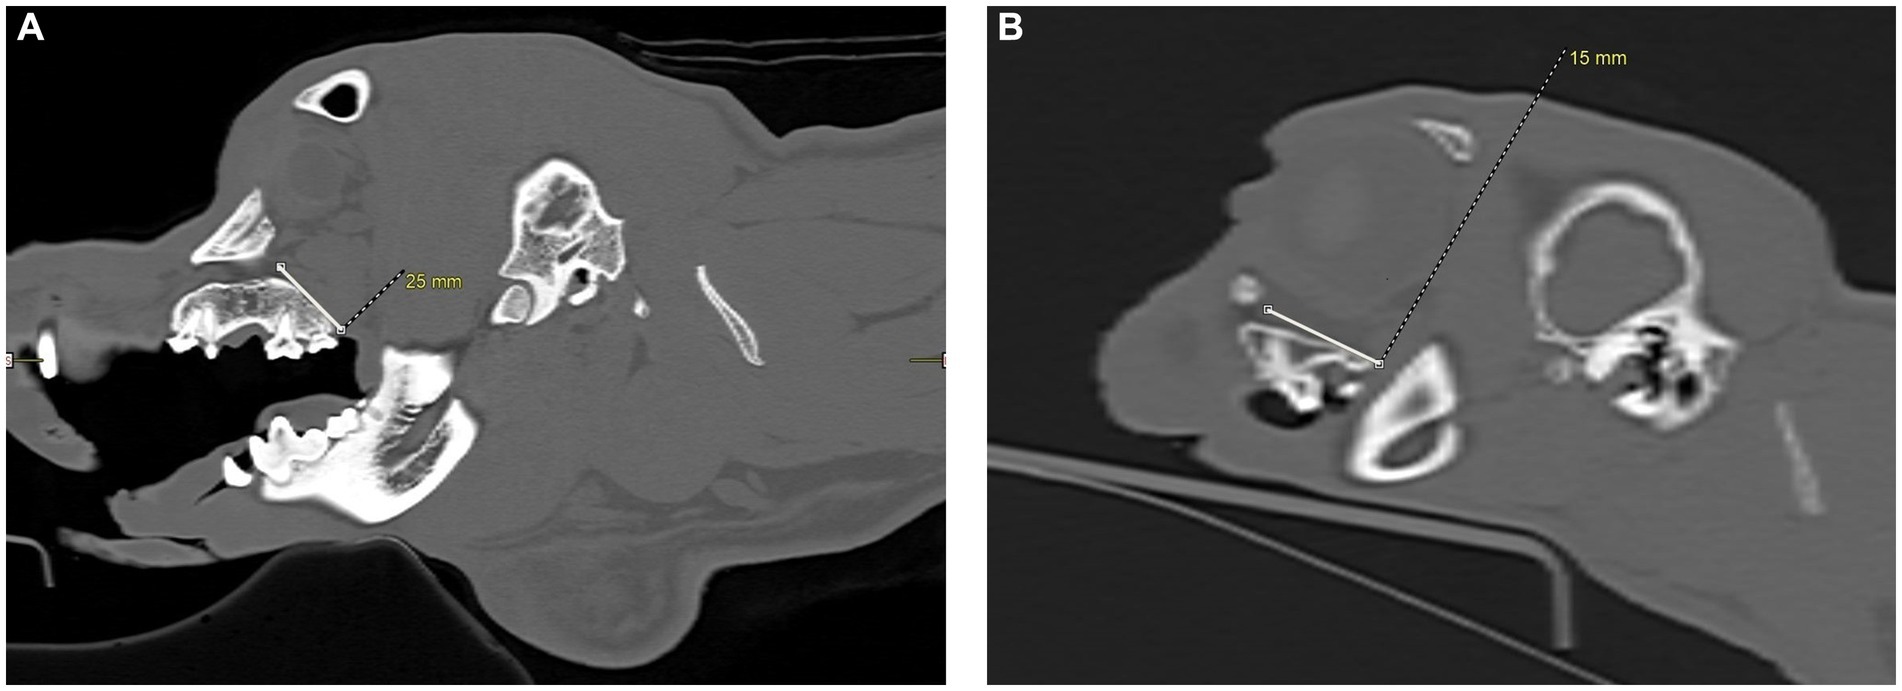

Figure 5

CT scans labeled A and B show sagittal views of a dog and cat skull. Image A highlights a 25 millimeter gap in a dog's skull, from the hard palate to an area in front of the eye, the maxillary foramen. Image B focuses on a 15 millimeter gap in a cat skull, from the hard palate to an area in front of the eye, the maxillary foramen. Bone structures and soft tissue are visible in grayscale, with measurements marked in yellow.

Figure 5. CT images showing measurements, in millimeters, taken from the caudal hard palate, immediately caudal to the maxillary second molar tooth in dogs and maxillary first molar tooth in cats, to the maxillary foramen. (A) Sagittal view of a dog skull showing the measurement from the caudal palate, immediately caudal to the maxillary second molar tooth, to the maxillary foramen. (B) Sagittal view of a cat skull showing the measurement, in millimeters, from the caudal palate, immediately caudal to the maxillary first molar tooth, to the maxillary foramen.